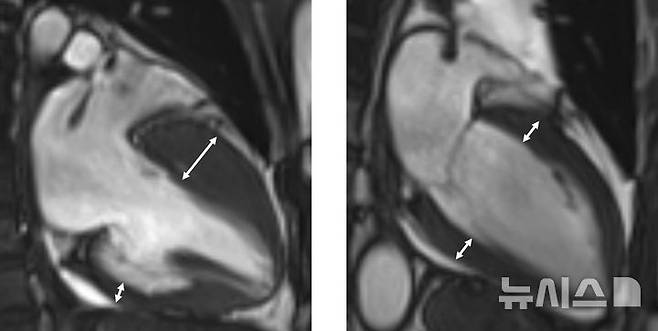

![[서울=뉴시스] 왼쪽부터 비후성 심근병증을 가진 환자의 자기공명영상, 정상 심장 자기공명영상. (사진= 고려대학교 안산병원 제공)](https://img1.daumcdn.net/thumb/R658x0.q70/?fname=https://t1.daumcdn.net/news/202511/13/newsis/20251113010250668kktc.jpg)

진단은 심장초음파, 자기공명영상 등 영상검사를 통해 이뤄지며, 비후된 심근 내에 섬유화가 진행돼 있거나, 근육조직이 지방조직으로 변성이 돼 있는 상태가 관찰된다. 하지만 이 같은 조직변성이 없는 비후성 심근병증도 있는 만큼 전문의의 종합적 판단이 중요하다.